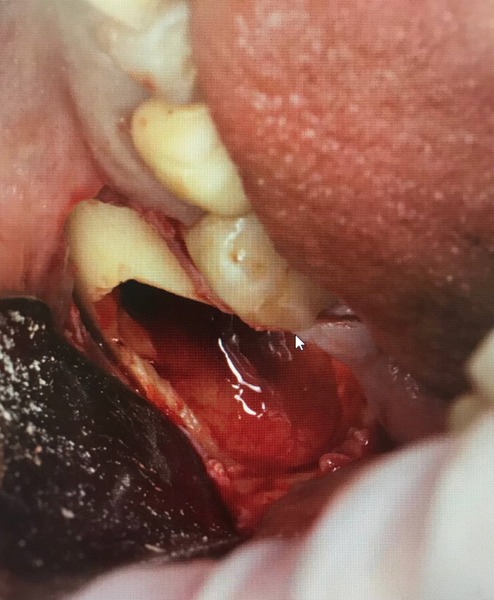

А тут трогаем, потому что мешают

Выглядит это всё вот так. Результат получается потрясный!